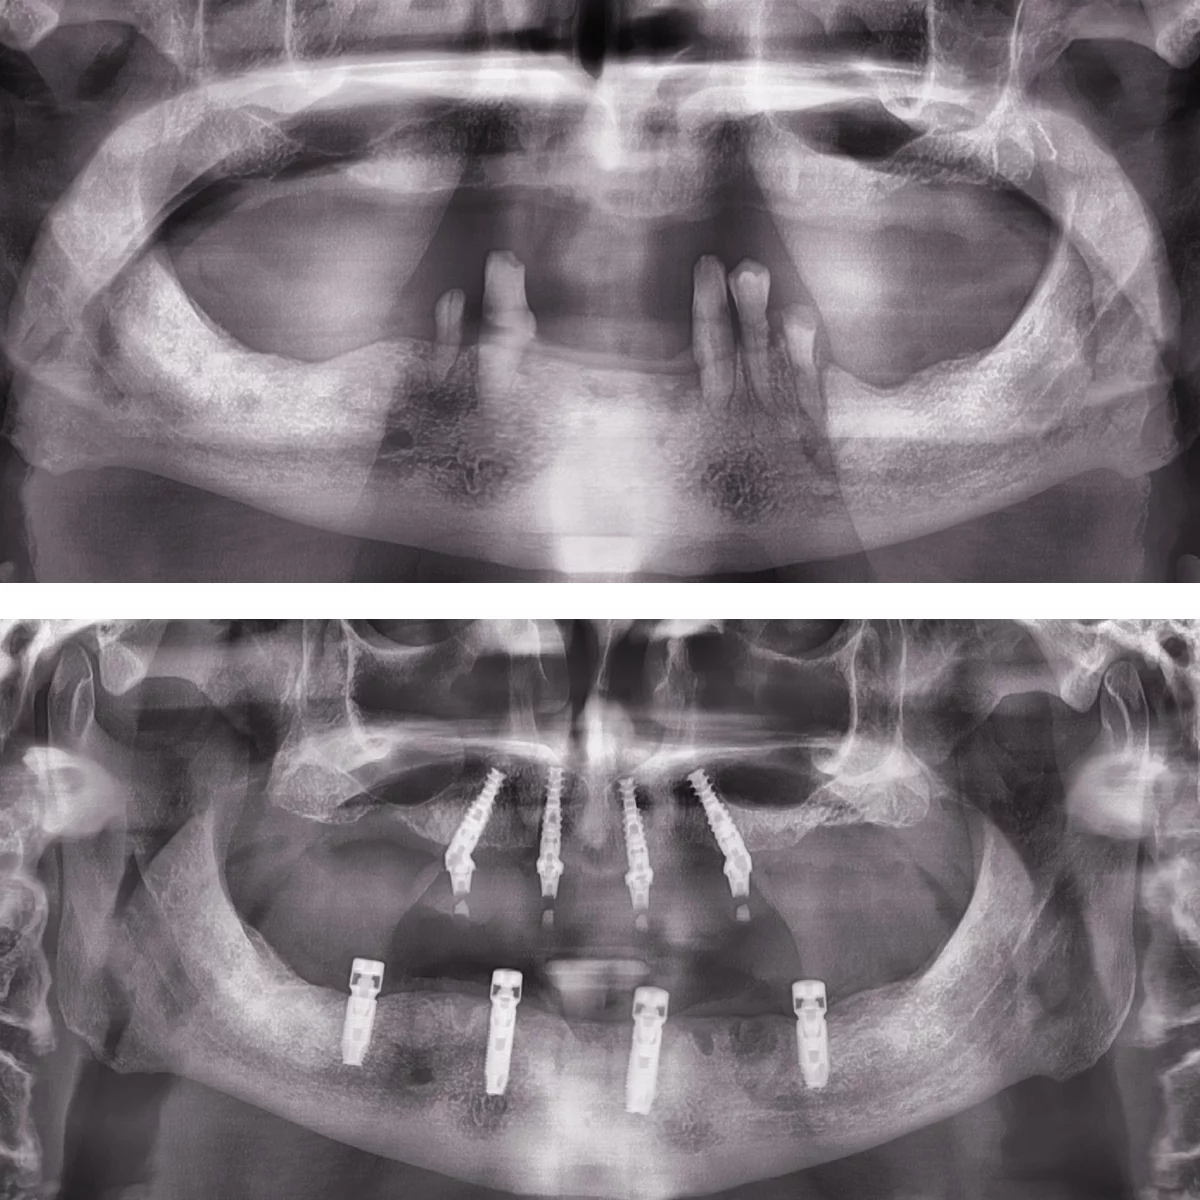

Dinți Ficși în 8-24 de ore pe implanturi dentare cu tehnica All-on-4/All-on-6 este cea mai eficientă și rapidă metodă de restaurare totală a danturii.

Intervenția chirurgicală explicată

Care sunt etapele până la efectuarea intervenției de dinți ficși

- Intervenția chirurgicală